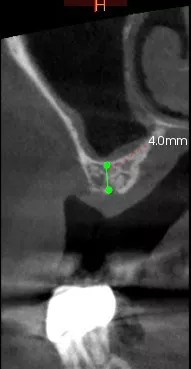

Therefore, we opted for a shortened dental arch that would replace 25 and 26 but not 27. We decided to perform simultaneous sinus floor augmentation and implant placement, as there was only 4 mm of native bone at the implant sites.

1-2. Panoramic radiography and cone-beam computed tomography showing vertical bone loss. With only 4 mm of sinus floor bone, implant placement was not feasible.